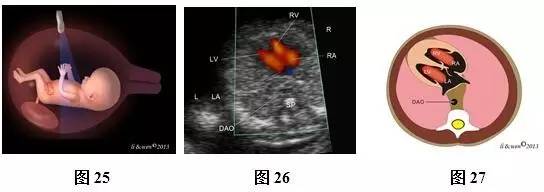

(二)11~13+6孕周胎儿心脏扫查方法及观察内容

超声扫查方法:声束从心尖部进入,在膈肌稍上方横切胸腔(图25),即获得心尖四腔心切面(图26,27);声束平面向胎儿头侧偏斜(图28),即可获得三血管气管切面(threevessels and trachea view,3VT,图29,30)图像。

标准切面判断标准:四腔心切面显示心脏四个腔室,可见二、三尖瓣启闭运动。3VT切面显示从左向右依次显示肺动脉、主动脉弓和上腔静脉,肺动脉和主动脉弓排列呈“V”形,两者血流方向相同。彩色多普勒血流成像对这些结构显示更清楚。

主要观察内容:四腔心切面主要观察心脏位置,心尖指向,心脏轴,左、右房室大小,房室瓣情况等。3VT切面主要观察肺动脉、主动脉弓、上静脉排列关系,血管数目,血管径线,血流方向等。

注:LV为左心室;RV为右心室;LA为左心房;RA为右心房;DAO为降主动脉;MPA为主肺动脉;ARCH为主动脉弓;T为气管;SVC为上腔静脉;R为右侧;L为左侧

图25~30 11~13+6孕周胎儿心脏扫查方法、观察内容及声像图及模式图。图25四腔心切面扫查模式图;图26、27四腔心切面彩色多普勒声像图及模式图;图28 3VT切面扫查模式图;图29、30 3VT彩色多普勒声像图及模式图